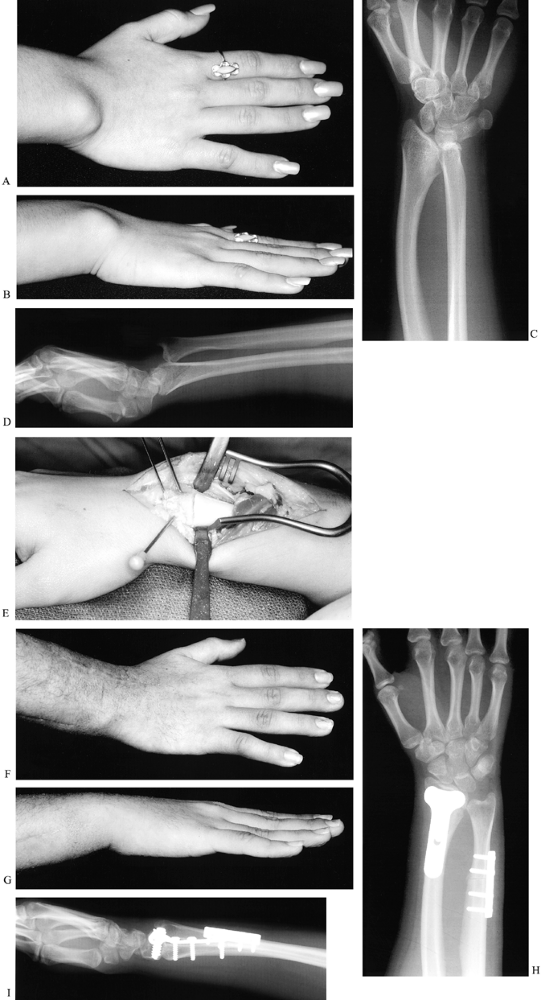

Nonvascularized toe proximal phalanx transfer (Fig. 69.26).

Figure 69.26. Nonvascularized toe proximal phalanx transfers. A: Preoperative palmar view. B: Preoperative radiograph view, with soft-tissue tubes distal to metacarpals. C: Postoperative radiograph, following toe proximal phalanx transfers to index, long, ring, and small fingers. D: Palmar view, 2 years after phalanx transfer. E:

Radiograph, 2 years after phalanx transfer. Note the open physis of the

ring phalanx, and the resorption of the tips of the long and small

phalanges. F: Feet, 4 years after phalanges were harvested from third and fourth toes of both feet.-